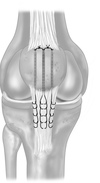

patellar tendon rupture repair options and outcomes, most common complication, most important prognostic factor

*Suture anchor tendon repair*: atleast 2 achors, **higher ultimate load to failure and less gap formation compared to transosseus fixation.** Transosseus repair: not as good, see image outcomes biomechanical studies have shown **less gap formation with suture anchor repair** compared to transosseous repair; clinical studies have shown** a significant decrease in re-rupture rate with use of suture anchor compared to transosseous repair.** complication: #1 **knee stiffness** MUA if flexion less than 120 at 6-12 weeks post op Lyssis of adhesion if less than 120 after 12 weeks post op #2 Quadatrophy: does not compromise return of strength most important prognostic factor for complete tears is ** timing of repair**